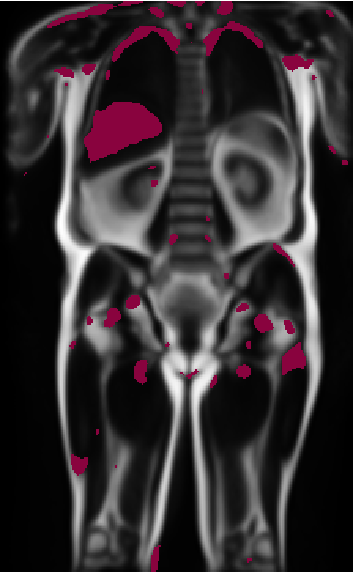

Distributional Changes in Label Atlases

Refer to caption

Figure 9: Significant p​v​a​l<0.01π‘π‘£π‘Žπ‘™0.01pval<0.01 voxels in the visceral fatty tissue for patients with coronary artery disease (middle row) and type 2 diabetes (bottom row) for the male overweight group. The first row shows the atlas, e.g. the average fat distribution, and each column shows a different slice (i) in the image. The purple values represent more fat in the pathological group and the cyan represents less. These results show that there is significantly more visceral fat in the CAD and diabetic group than in the healthy one.

As a second application, we perform a similar analysis with visceral fat distribution. We utilise the abdominal visceral fat maps from healthy subjects previously used to build the atlas of the male overweight group and test them against diseased subjects. The pathological subgroups are selected and registered in the same fashion as previously explained, with the additional criteria that they contain the target disease – in our case, coronary artery disease (CAD) or type 2 diabetes. We select 200200200 subjects with CAD, 200200200 subjects with diabetes and 200200200 subjects from the healthy atlas group. Similarly to before, each fat label map is spatially normalised with a Gaussian kernel, and voxel-wise one-sided t-tests are subsequently performed between the healthy and the pathological group. We perform two types of one-sided t-tests; one assesses a higher mean, which indicates more fat in the pathological group and one the opposite: less fat in the pathological group. The results for both tests are shown in Figure 6, where the significant values for more fat are visualised in purple and those for less fat in cyan. We then perform a FDR correction to the P-map and retain the significant p-values p​v​a​l<0.01π‘π‘£π‘Žπ‘™0.01pval<0.01. Figure 6 shows the significant voxels overlayed on the anatomical atlas for the overweight male subgroup. The first column shows the fat label atlas overlayed on the water-contrast anatomical atlas; the second column shows the significant voxels for more and less fat for CAD; and the last column for type 2 diabetes. Each row is a visualisation of a different coronal slice. A more comprehensive set of slices can be visualised in the supplementary material in Figure 9.

We see a significant increase in organ-associated visceral fat around the kidneys, as well as in mesenteric fat and within the lower pelvis (Figure 9). Areas of lower fat content are found in the marginal area, as well as on the lower liver border. Moreover, comparing both pathological groups, the diabetic group shows a larger increase in mesenteric fat than the CAD group compared to the atlas. This increase in visceral fat for these pathological groups is also observed in other studies[nakamura1994contribution, despres2007cardiovascular], which further confirms the value of these results. We attribute the marginal speckles (e.g., in the shoulders and lungs) to noise arising from either misregistration or remaining false positives from the t-test.